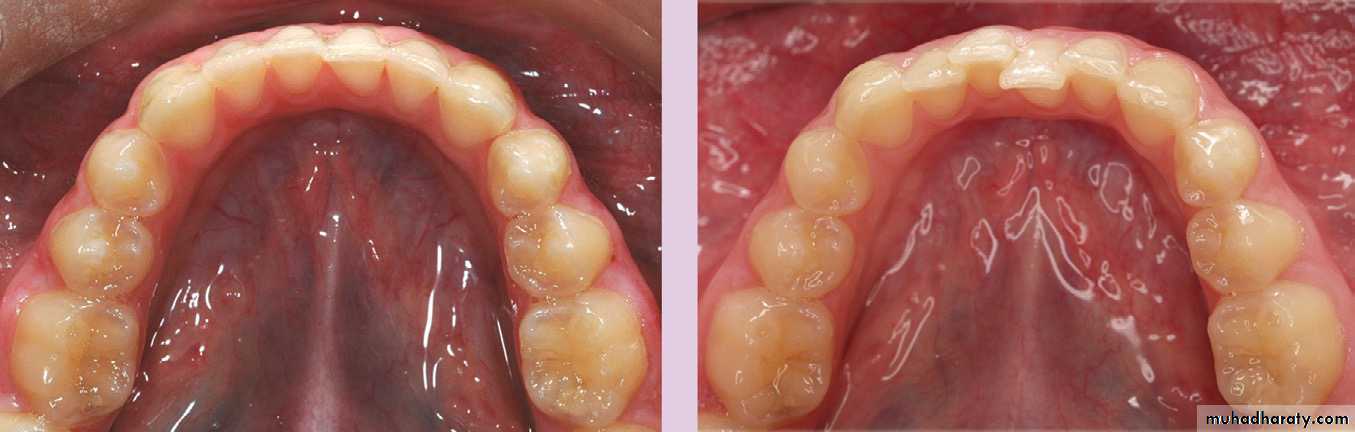

These teeth usually present in their crept in a rotated manner, this is to occupy a less space in the child’s mouth; so that, when they erupt, they will erupted in a spaced conditions, and these spaces usually present at the mesial aspect of the upper canine and the distal aspect of the lower canine.

These spaces are termed as primary spaces or anthropoid spaces, since it looks like the spaces that are present between the teeth of the higher Apes.

In summery the complete primary dentition is classically associated with a number of characteristic features:

• The arches are semi-circular in shape;

• The incisors are spaced, upright and associated with a positive overjet and overbite;• Primate or anthropoid spaces are present, mesial to the maxillary primary canines and distal to the mandibular canines;

• The molar and canine relationship is class I; and

• The distal edges of the second primary molars are flush in the vertical plane.